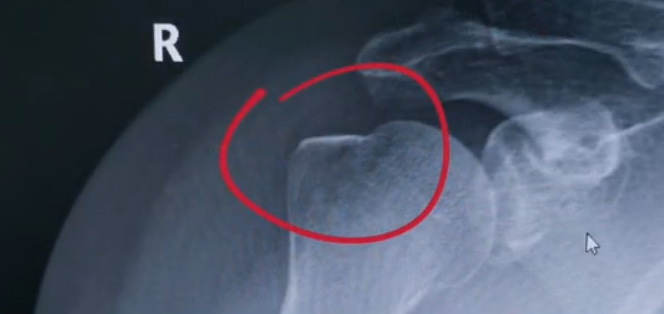

肩關(guān)節(jié)的X射線片子,看到?jīng)]有明顯的骨折,但是實(shí)際上已經(jīng)骨折了。那么是如何發(fā)現(xiàn)的呢?醫(yī)生對(duì)于做出疾病診斷的時(shí)候,會(huì)選擇什么樣的檢查方式。也更好的配合醫(yī)生,來(lái)解決問(wèn)題。1米高的地方摔了下來(lái),右側(cè)肩關(guān)節(jié)與地面相撞受傷了。當(dāng)時(shí)的胳膊還能活動(dòng),疼痛感很明顯,但是在家觀察了一天,這個(gè)腫脹沒(méi)有明顯的加重。然而問(wèn)題是什么呢?疼痛始終不能緩解,所以就需要到醫(yī)院檢查。醫(yī)生查看關(guān)節(jié)的受限也很明顯,尤其做外展這個(gè)動(dòng)作的時(shí)候,幾乎沒(méi)辦法自行完成。肩關(guān)節(jié)內(nèi)的這個(gè)韌帶和肌腱可能還沒(méi)有發(fā)生嚴(yán)重的損傷。

首先做一個(gè)普通的X光檢查,看一看有沒(méi)有大的骨折或大的問(wèn)題。結(jié)果是沒(méi)有發(fā)現(xiàn)太嚴(yán)重骨折損傷問(wèn)題。結(jié)合病史,還是有點(diǎn)疑惑。因?yàn)樘鄣奶珔柡Α光檢查和他的疼痛之間不匹配,患者沒(méi)有骨頭的損傷,疼痛不至于達(dá)到這么嚴(yán)重的一個(gè)程度。是否有一種情況掩蓋住了病情。這也是X線檢查的通病。x光檢查它是一個(gè)二維的檢查,有可能患者肩關(guān)節(jié)啊發(fā)生了骨折。但是它的位置被前方或者側(cè)方的這個(gè)骨頭遮擋住了。不是立體的就沒(méi)辦法看到后方的情況。想要更加進(jìn)一步的明確問(wèn)題,判斷是否有骨頭的損害怎么辦?

進(jìn)一步就是查CT,可以更全面的角度去判斷問(wèn)題的所在。就會(huì)發(fā)現(xiàn)是否骨折可以看到確實(shí)存在著骨折,還好骨折不算嚴(yán)重??梢哉f(shuō)是一個(gè)骨裂。這個(gè)肩關(guān)節(jié)與地面撞擊的時(shí)候,暴力沒(méi)有達(dá)到那么強(qiáng)。讓骨頭整個(gè)發(fā)生一個(gè)巨大的斷裂,而是造成了一個(gè)小的劈裂。適當(dāng)?shù)倪M(jìn)行一些抗炎止痛藥的使用。適當(dāng)?shù)倪M(jìn)行一些消腫治療,患者癥狀也就消失了。